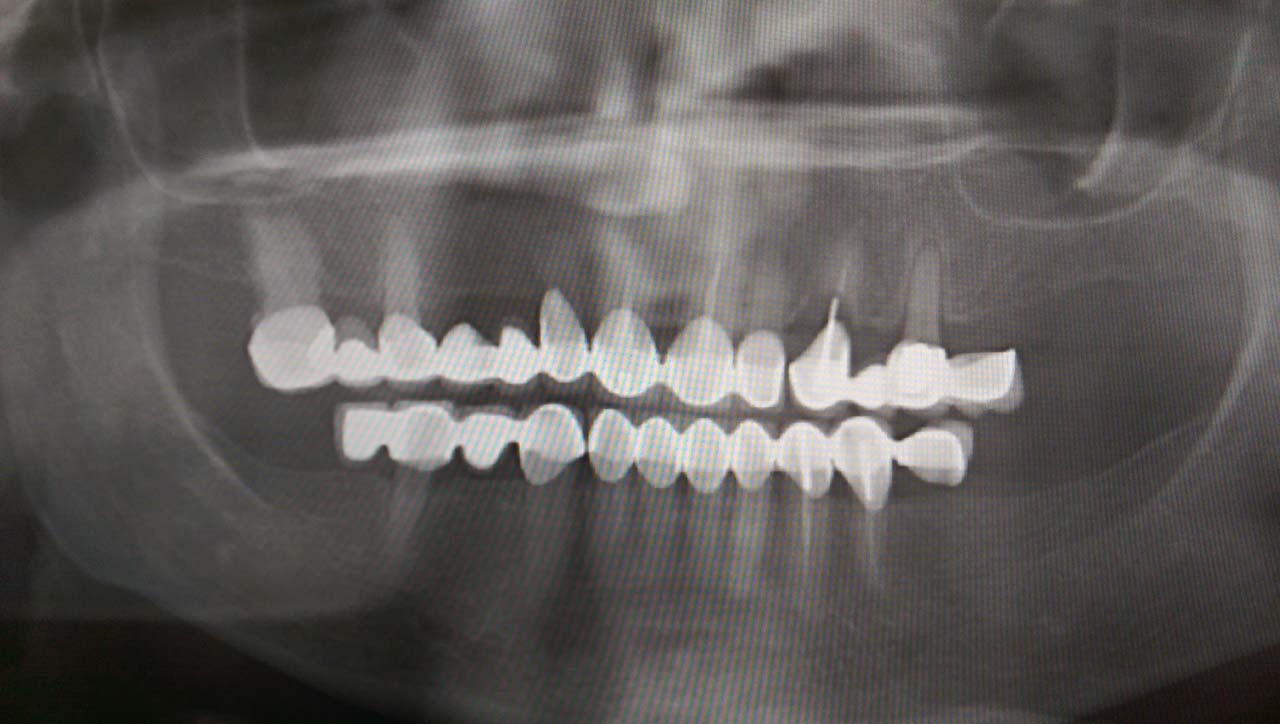

Teljes szájüregi rehabilitáció két lépésben

Ismét egy teljes szájüregi rehabilitáció két lépésben. Először az alsó fogak lettek kihúzva és azonnal implantálva, híddal ellátva, majd később a felső. IHDE svájci azonnal terhelhető implantátumok és cirkónium hidak. Dr. Kelemen Péter és a Symbion Fogtechnika közös munkája.